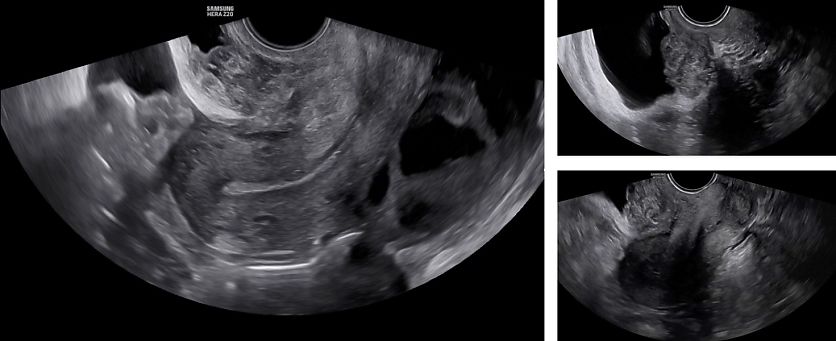

On ultrasound examination, typical endometriomas present as a cystic lesion with ground-glass echogenicity, with one to four locules and no solid components in a premenopausal patient (Figure 26). Of 713 histologically confirmed endometriomas in the International Ovarian Tumor Analysis (IOTA) studies, 65% were unilocular and 73% exhibited ground-glass echogenicity and 13% had low-level echogenicity.42 Atypical endometriomas are defined as unilocular-solid lesions with ground-glass echogenicity and a papillary projection, a color score of 1 or 2 and no vascularization inside the papillary projection (Figure 27).5 As per the recommendation of the IDEA consensus, the presence or absence of endometriomas should be described, as well as their number, size in three orthogonal planes and their ultrasound appearance according to International Ovarian Tumor Analysis (IOTA) terminology.43 Assessing vascularization by power Doppler may help in the differentiation between an endometrioma, a corpus luteum and a malignant lesion.44 A corpus luteum is characterized by strong circumferential blood flow (‘ring of fire’) and will generally resolve spontaneously after the menstrual cycle, unlike an endometrioma.

26

Ultrasound images of endometriomas with typical features of ground-glass echogenicity, up to four locules and no solid components.

27

Ultrasound images of atypical endometrioma, with the presence of a non-vascularized papillary projection.